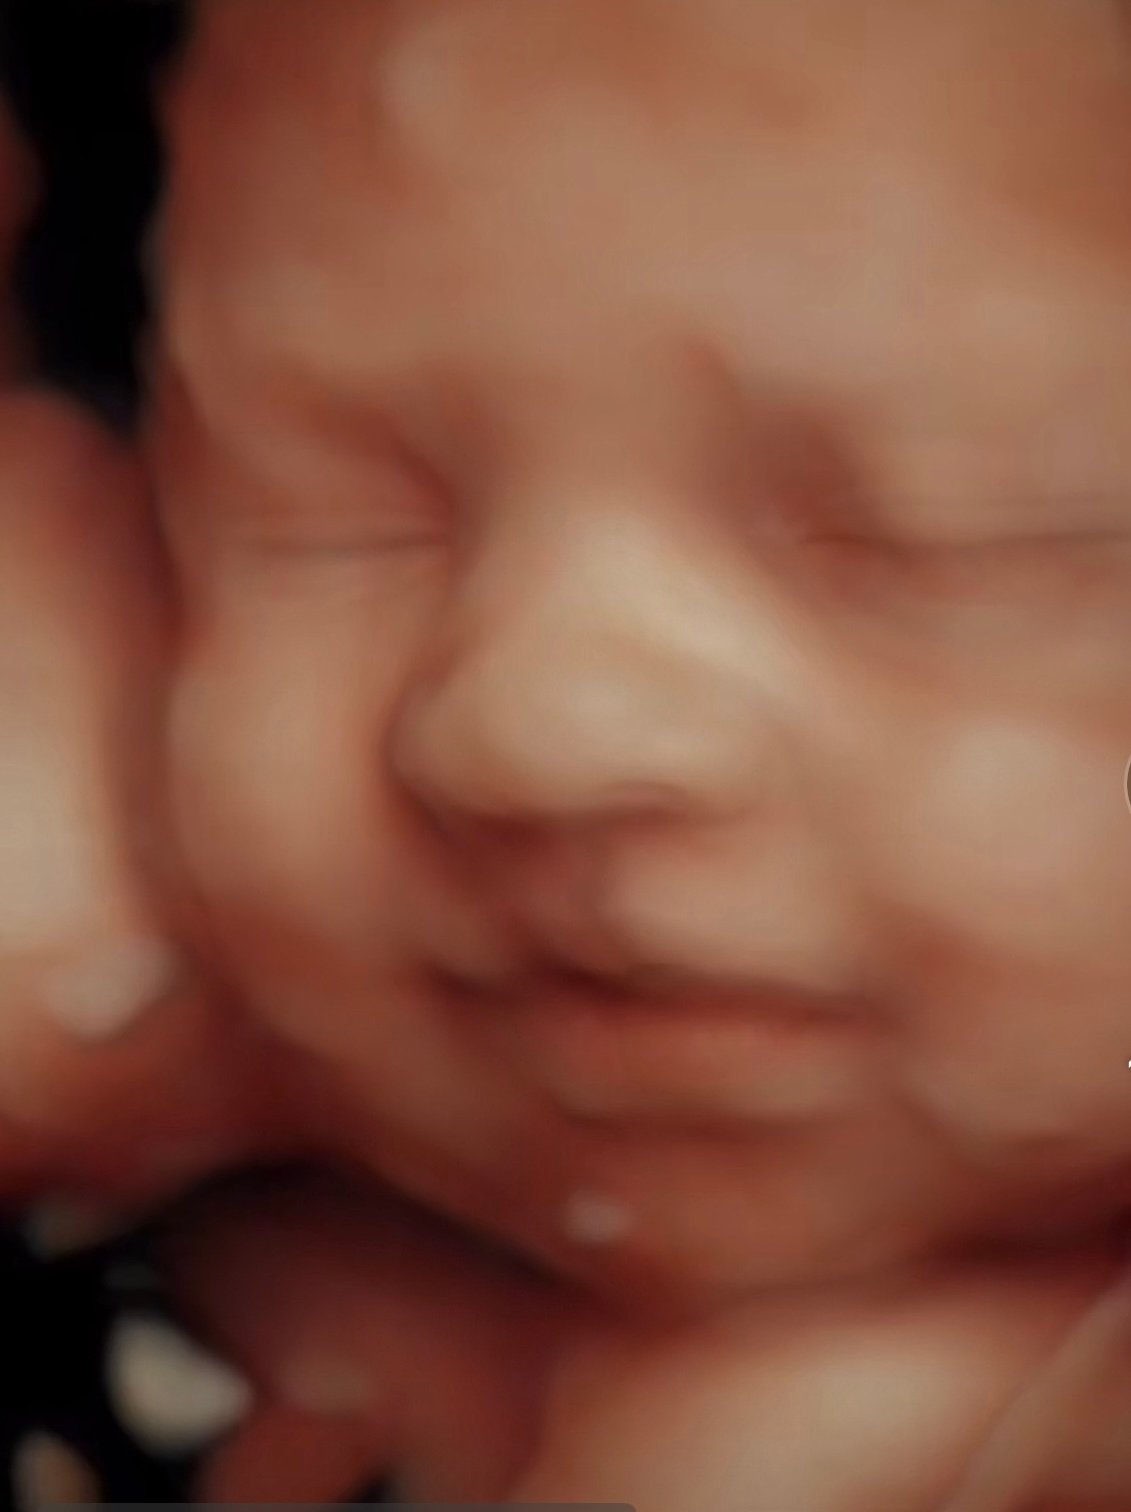

Elective 2D, 3D and 4D Ultrasounds in Tampa.

See your baby in 2D, 3D, and 4D. Experience the joy of meeting your baby before birth. Our elective ultrasounds are designed to create unforgettable moments for families. Enjoy our cozy environment of peace in an ultrasound in Tampa or Central Florida.

Our elective 4D sessions capture your baby’s real movements and transform them into breathtaking 8K baby portraits, memories you can keep forever.